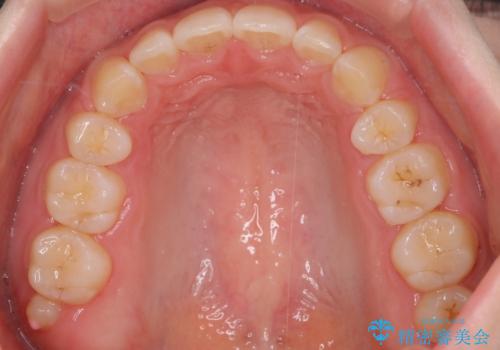

上下左右の歯を1本ずつ、合計4本抜歯しして前歯を後方に下げて、口元の突出感を改善する計画としました。

前歯をしっかり下げることで、口元がすっきりしました。